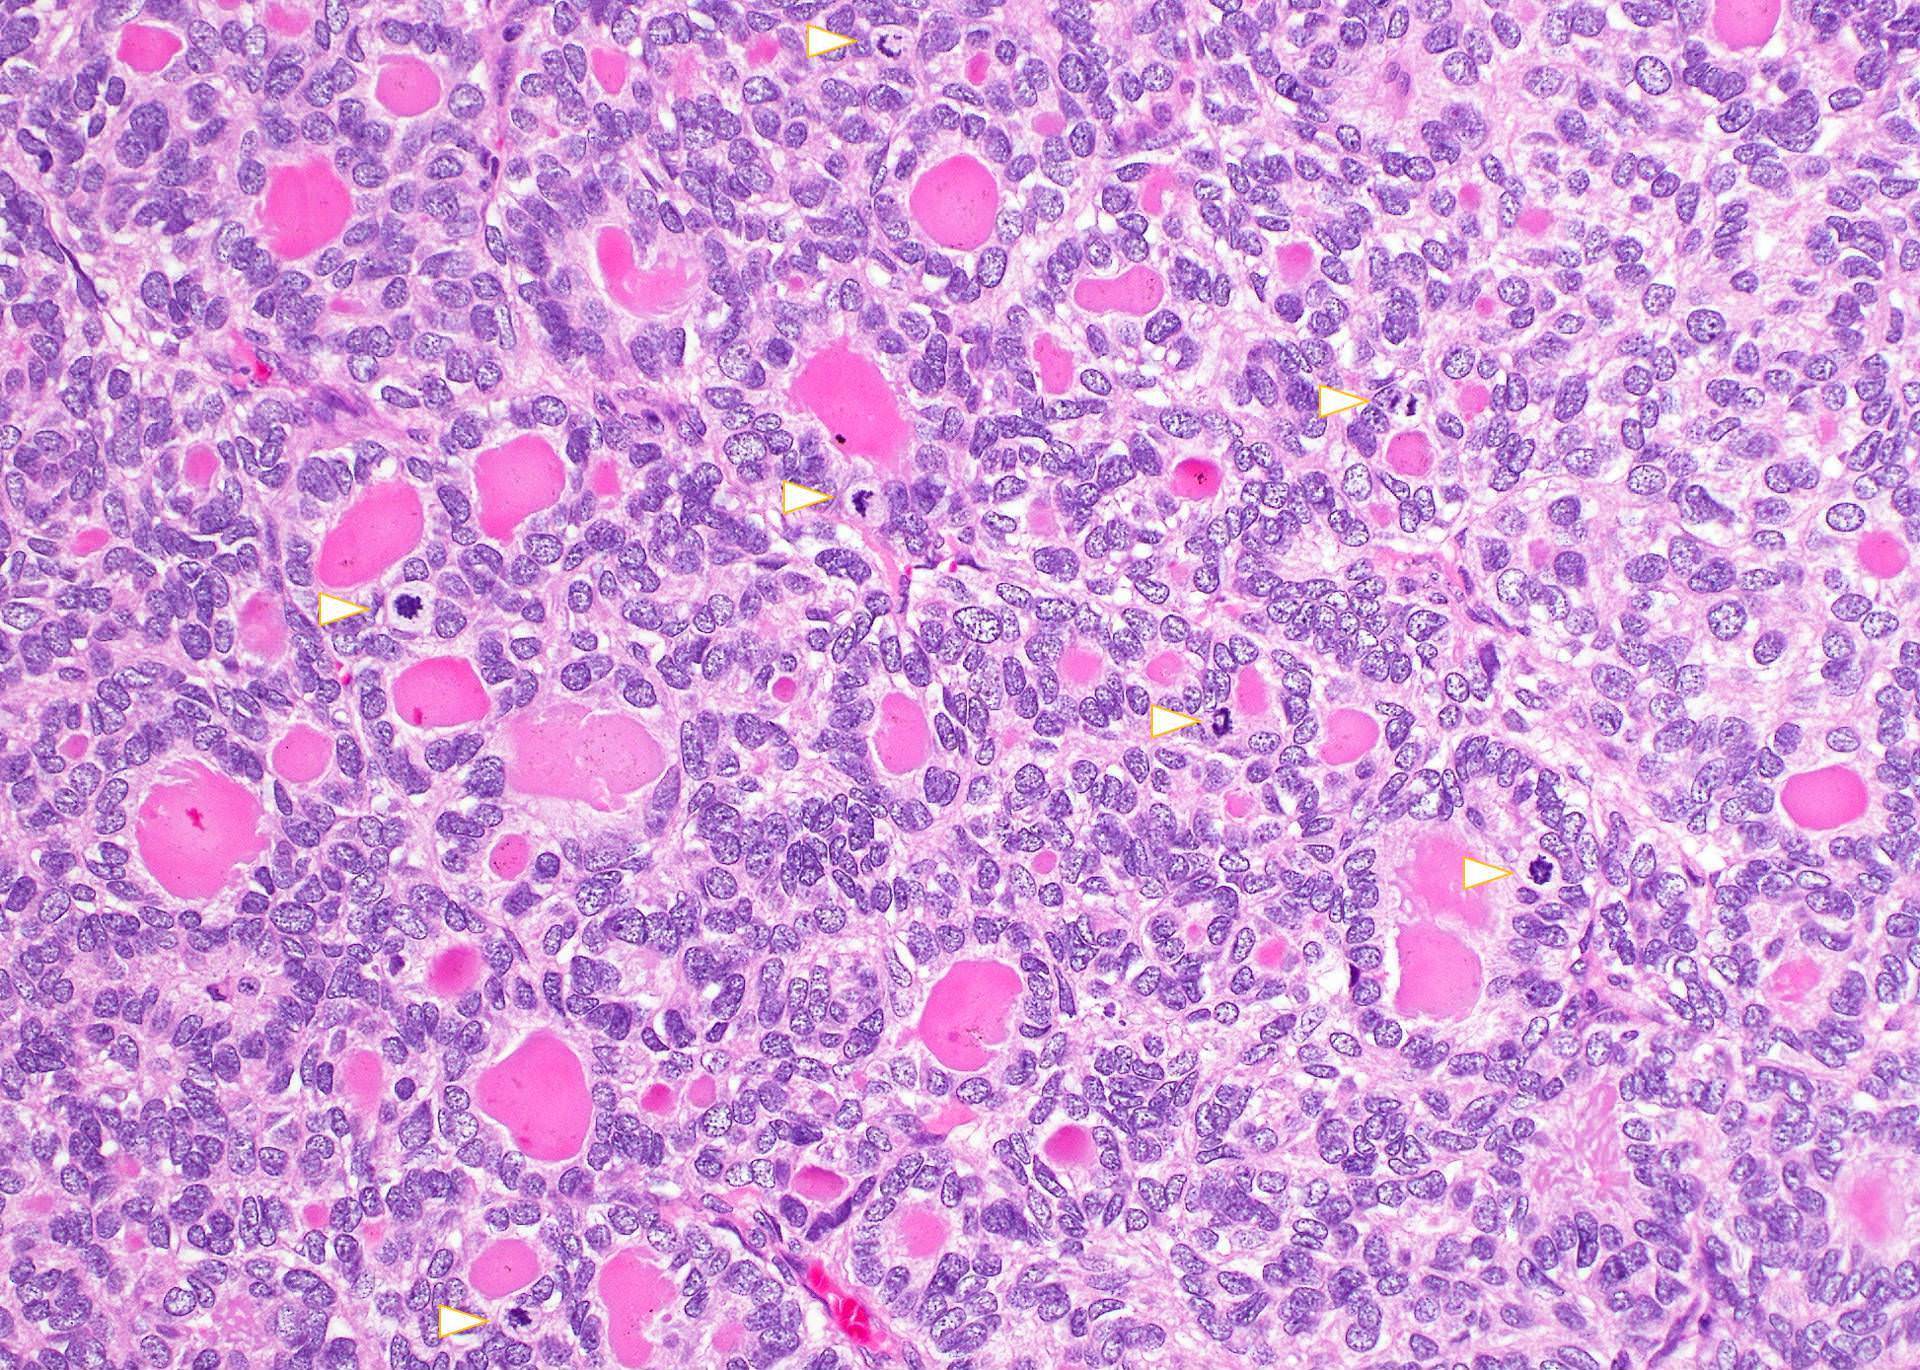

Microscopic (histologic) images

Contributed by Andrey Bychkov, M.D., Ph.D., Mark R. Wick, M.D. and AFIP

False angioinvasion

Capsular vessel with tumor

Vascular invasion

Tumor in vascular space

Transcapsular penetration

Invasion through tumor capsule

Propagation of tumor embolus

Extensive necrosis

Tumor necrosis

Unusual brisk mitotic activity

TTF1: bone metastasis

Moderate pleomorphism

Mucin production

Capsular invasion

Metastases to iliac bone

Thick, irregular capsule

• Trabecular or solid pattern of follicles (small, normal sized or large - microfollicular, normofollicular or macrofollicular respectively)

• No nuclear features of papillary thyroid carcinoma

• Invasion of adjacent thyroid parenchyma, capsule (complete penetration) or blood vessels (in or beyond the capsule)

• Capsular invasion: capsule is typically thickened and irregular, needs penetration through the capsule (full thickness), may have reactive pseudocapsule around the invasion edge, exclude FNA site

• Vascular invasion: vessel within or beyond capsule, tumor covered with endothelium, attached to the wall or with thrombus

• May have nuclear atypia, focal spindled areas, mitotic figures (< 3/10HPF)

• No necrosis

• Usually no squamous metaplasia, no psammoma bodies, no / rare lymphatic invasion